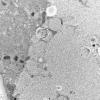

Pompe Disease (4)